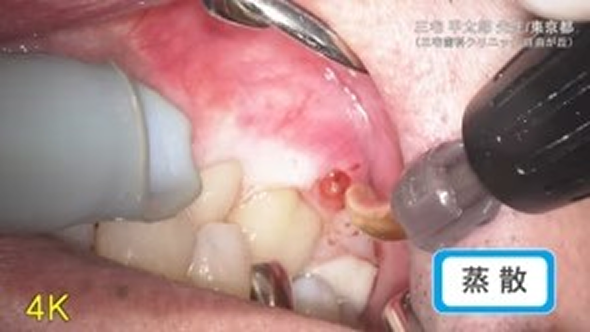

臨床例:炭酸ガスレーザーPRO-X(最大出力15W)を使用した先生の臨床例です。

蒸散